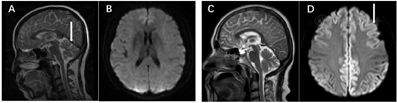

影像学检查:头常规MRI+SWI示,小脑欠饱满,余未见明显异常(图1)。经颅多普勒超声示,各血管血流频谱未见明显异常。